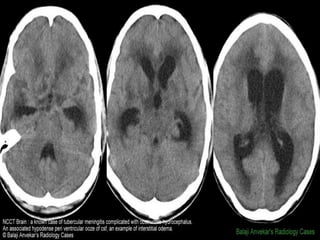

Interstitial odema

Infections

• Meningial enhancement and thickness,

extradural and subdural collection, with

associated communicating hydroceph.

• Focal parenchymal injury and abscess, mass

lesions with mass affects.

• Ventriculitis and diffuse cerebral odema.